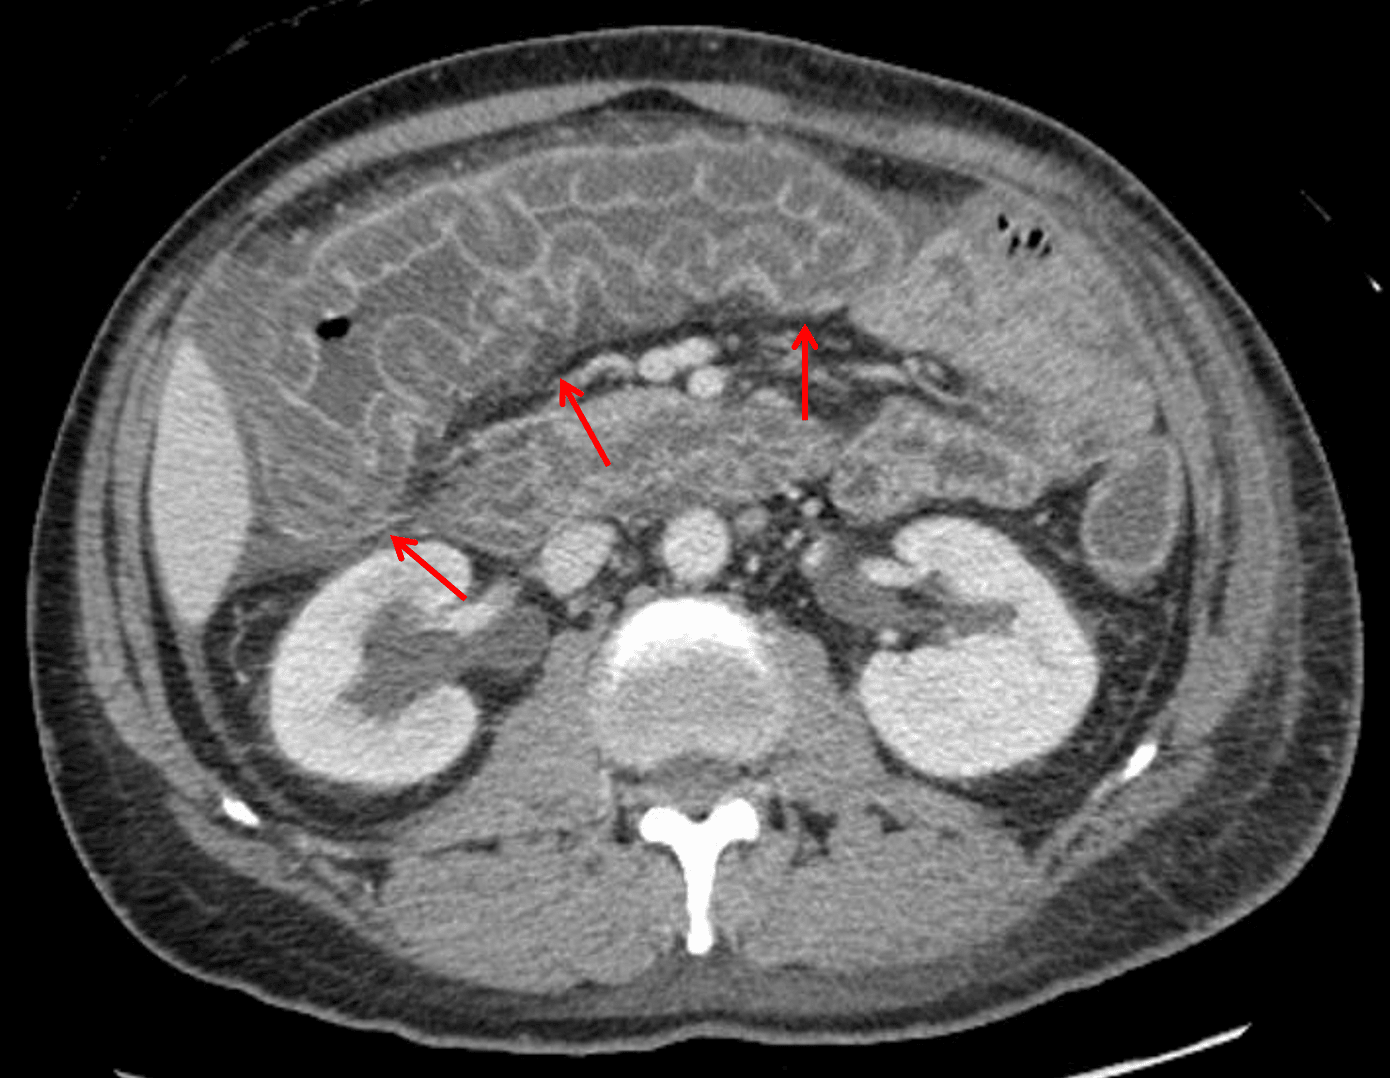

Lupus vasculitis: marked submucosal edema at the hepatic flexure and transverse colon resulting in a thumbprinting appearance of the mucosa (red arrows).